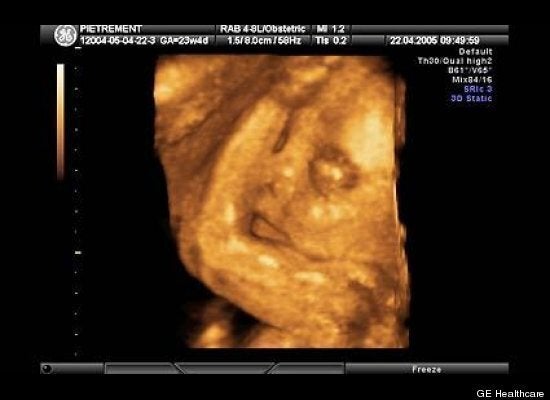

British Columbia Specific Information Your health care provider may request that you have one or more fetal ultrasound scans during your pregnancy . A fetal ultrasound scan is a medical procedure which uses sound waves to produce images of your baby in the womb . These images are used to determine the health and well-being of your baby .

The NT ultrasound can help you decide whether or not to have a diagnostic test such as amniocenteses, which will give you a definite diagnosis but carries a small risk of miscarriage . In order for the Medical Services Plan of British Columbia to cover this exam the patient must meet at least one of the following criteria: